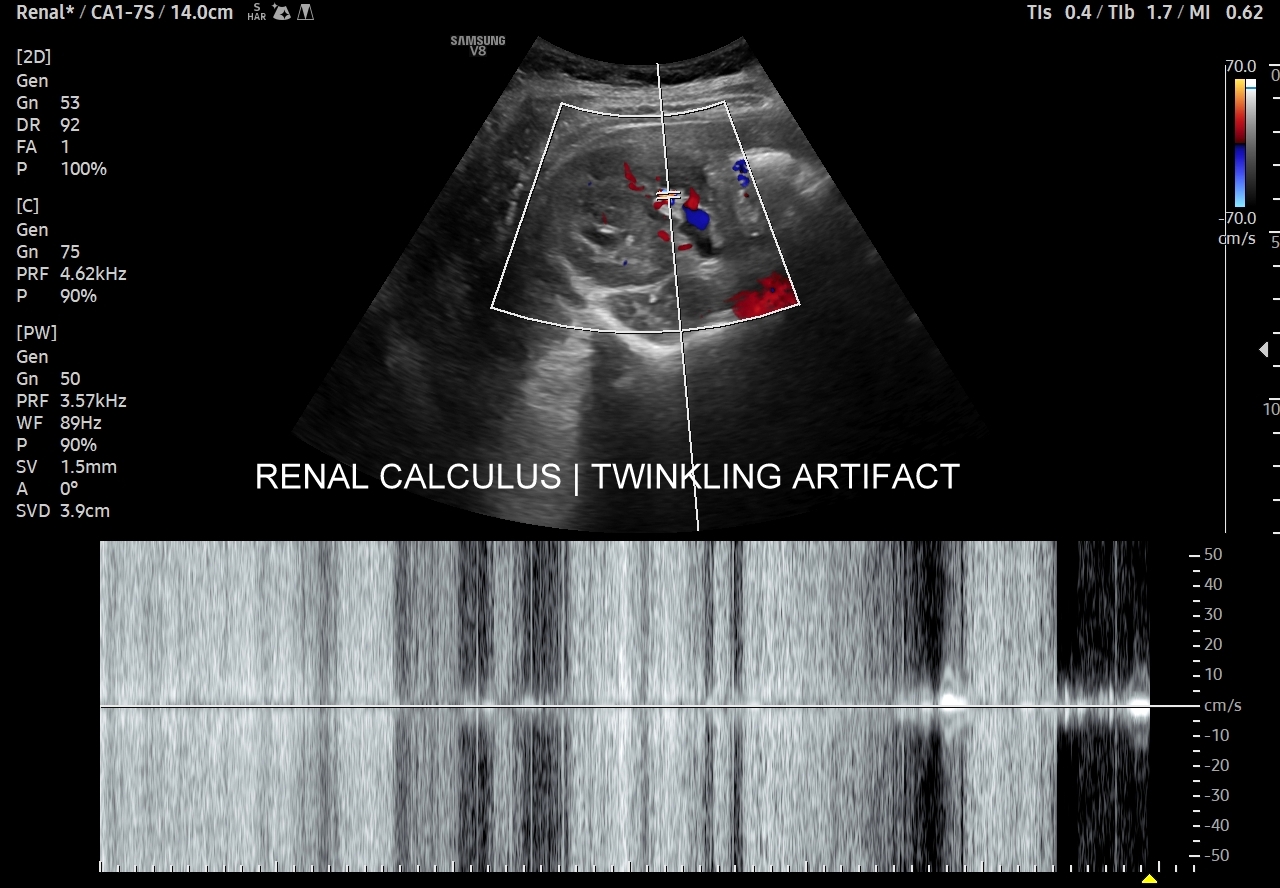

Ważnym trybem pomocniczym jest color-Doppler, w którym to trybie uzyskuje się tzw. artefakt migotania, często nawet na bardzo drobnych złogach niewidocznych w trybie B. Uzyskanie efektu migotania jest niestety zależne o jakości aparatury USG, a także od ustawień Dopplera i software’u.

W modalnościach dopplerowskich oprócz prezentacji color-Doppler artefakt migotania pojawia się także w trybie Dopplera spektralnego. Otóż po umieszczeniu bramki dopplerowskiej na złogu uzyskuje się charakterystyczny, dźwiękowy objaw trzeszczenia, a na obrazie wykresu wypełnienie sygnałem całego spektrum częstotliwości.